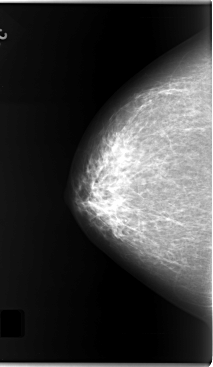

C_0124_1.RIGHT_CC

RIGHT_CC LINES 5872 PIXELS_PER_LINE 3408 BITS_PER_PIXEL 12 RESOLUTION 50 NON_OVERLAY